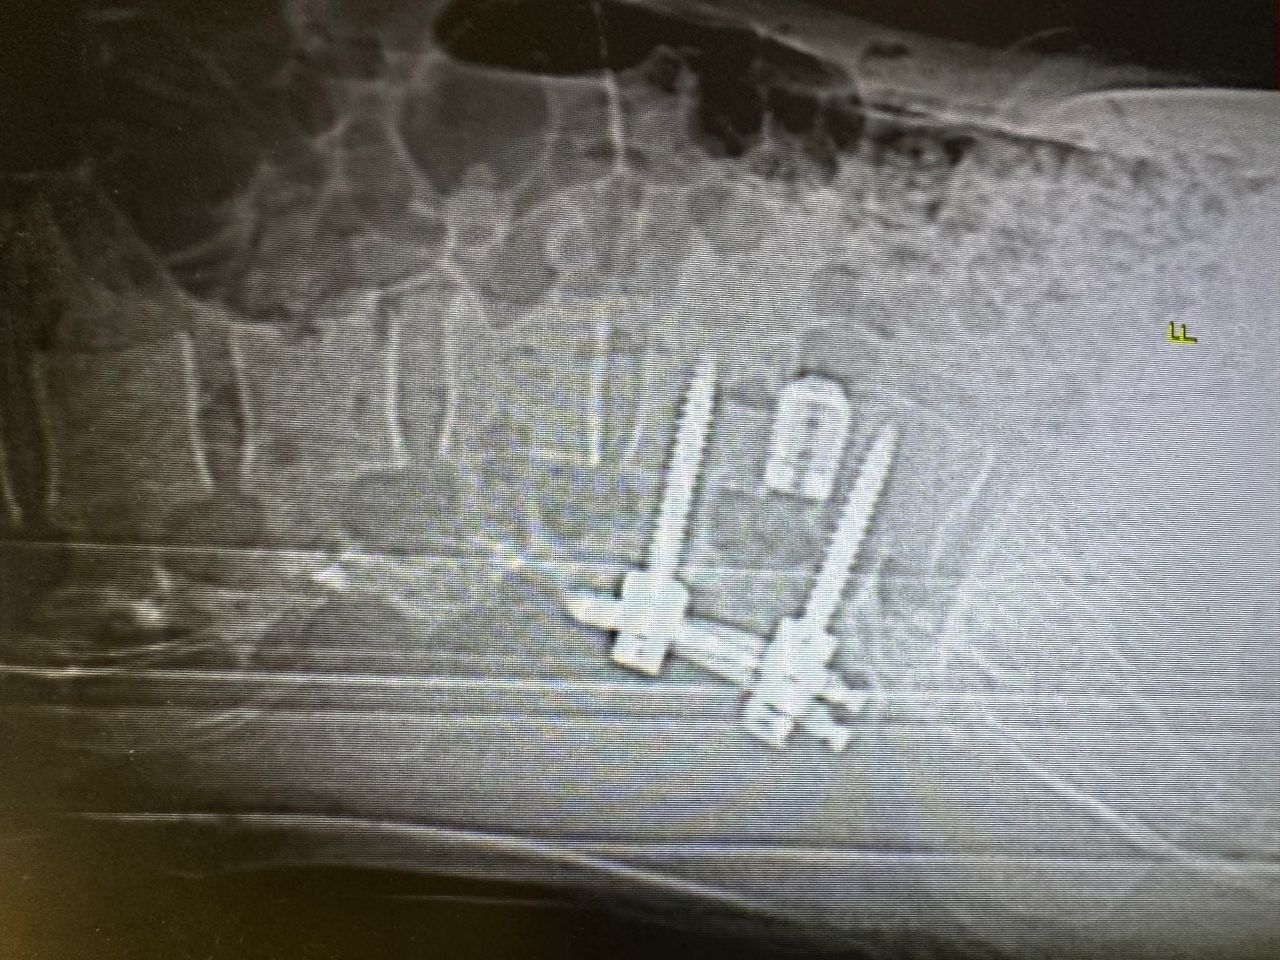

- Chirurgia Mininvasiva percutanea vertebrale - stabilizzazioni e artrodesi intersomatiche (per fratture vertebrali, spondilolistesi, instabilità vertebrali, discopatie)

- Vertebroplastica e cifoplastica percutanea (fratture vertebrali)